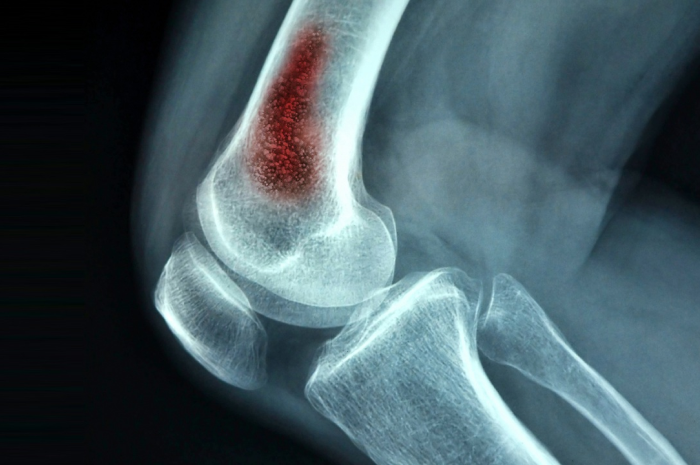

Bone Infection

Bone infection, also known as osteomyelitis, is a serious condition characterized by inflammation and infection of the bone and bone marrow. Bacteria or fungi can spread to the bone from an infection elsewhere in the body, such as a skin infection, urinary tract infection, or respiratory infection. Open fractures, surgical procedures, or penetrating injuries can introduce bacteria or fungi directly into the bone, leading to infection. Contiguous spread: Infections in adjacent tissues, such as soft tissues, joints, or prosthetic implants, can spread to the surrounding bone.